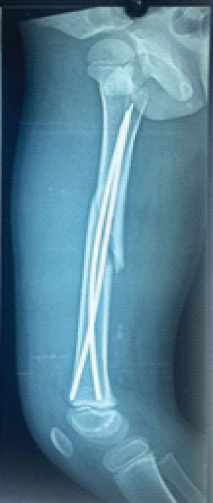

A Prospective Study of Comparison between Stable and Unstable Pediatric Femoral Shaft Fractures Treated With Titanium Elastic Nails

Parin Shah , Abhishek Sharma , Mohd Adnan , Sahil Shah , Ananya Chaudhary , Aarsh Shah

………………………………p.384-390